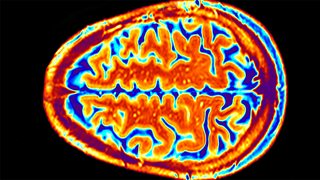

Professor Sophie Scott of University College London explains how MRI scanners work.